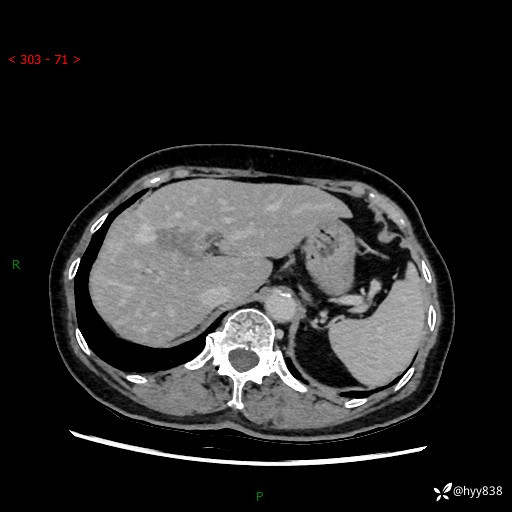

上腹部CT平扫+增强